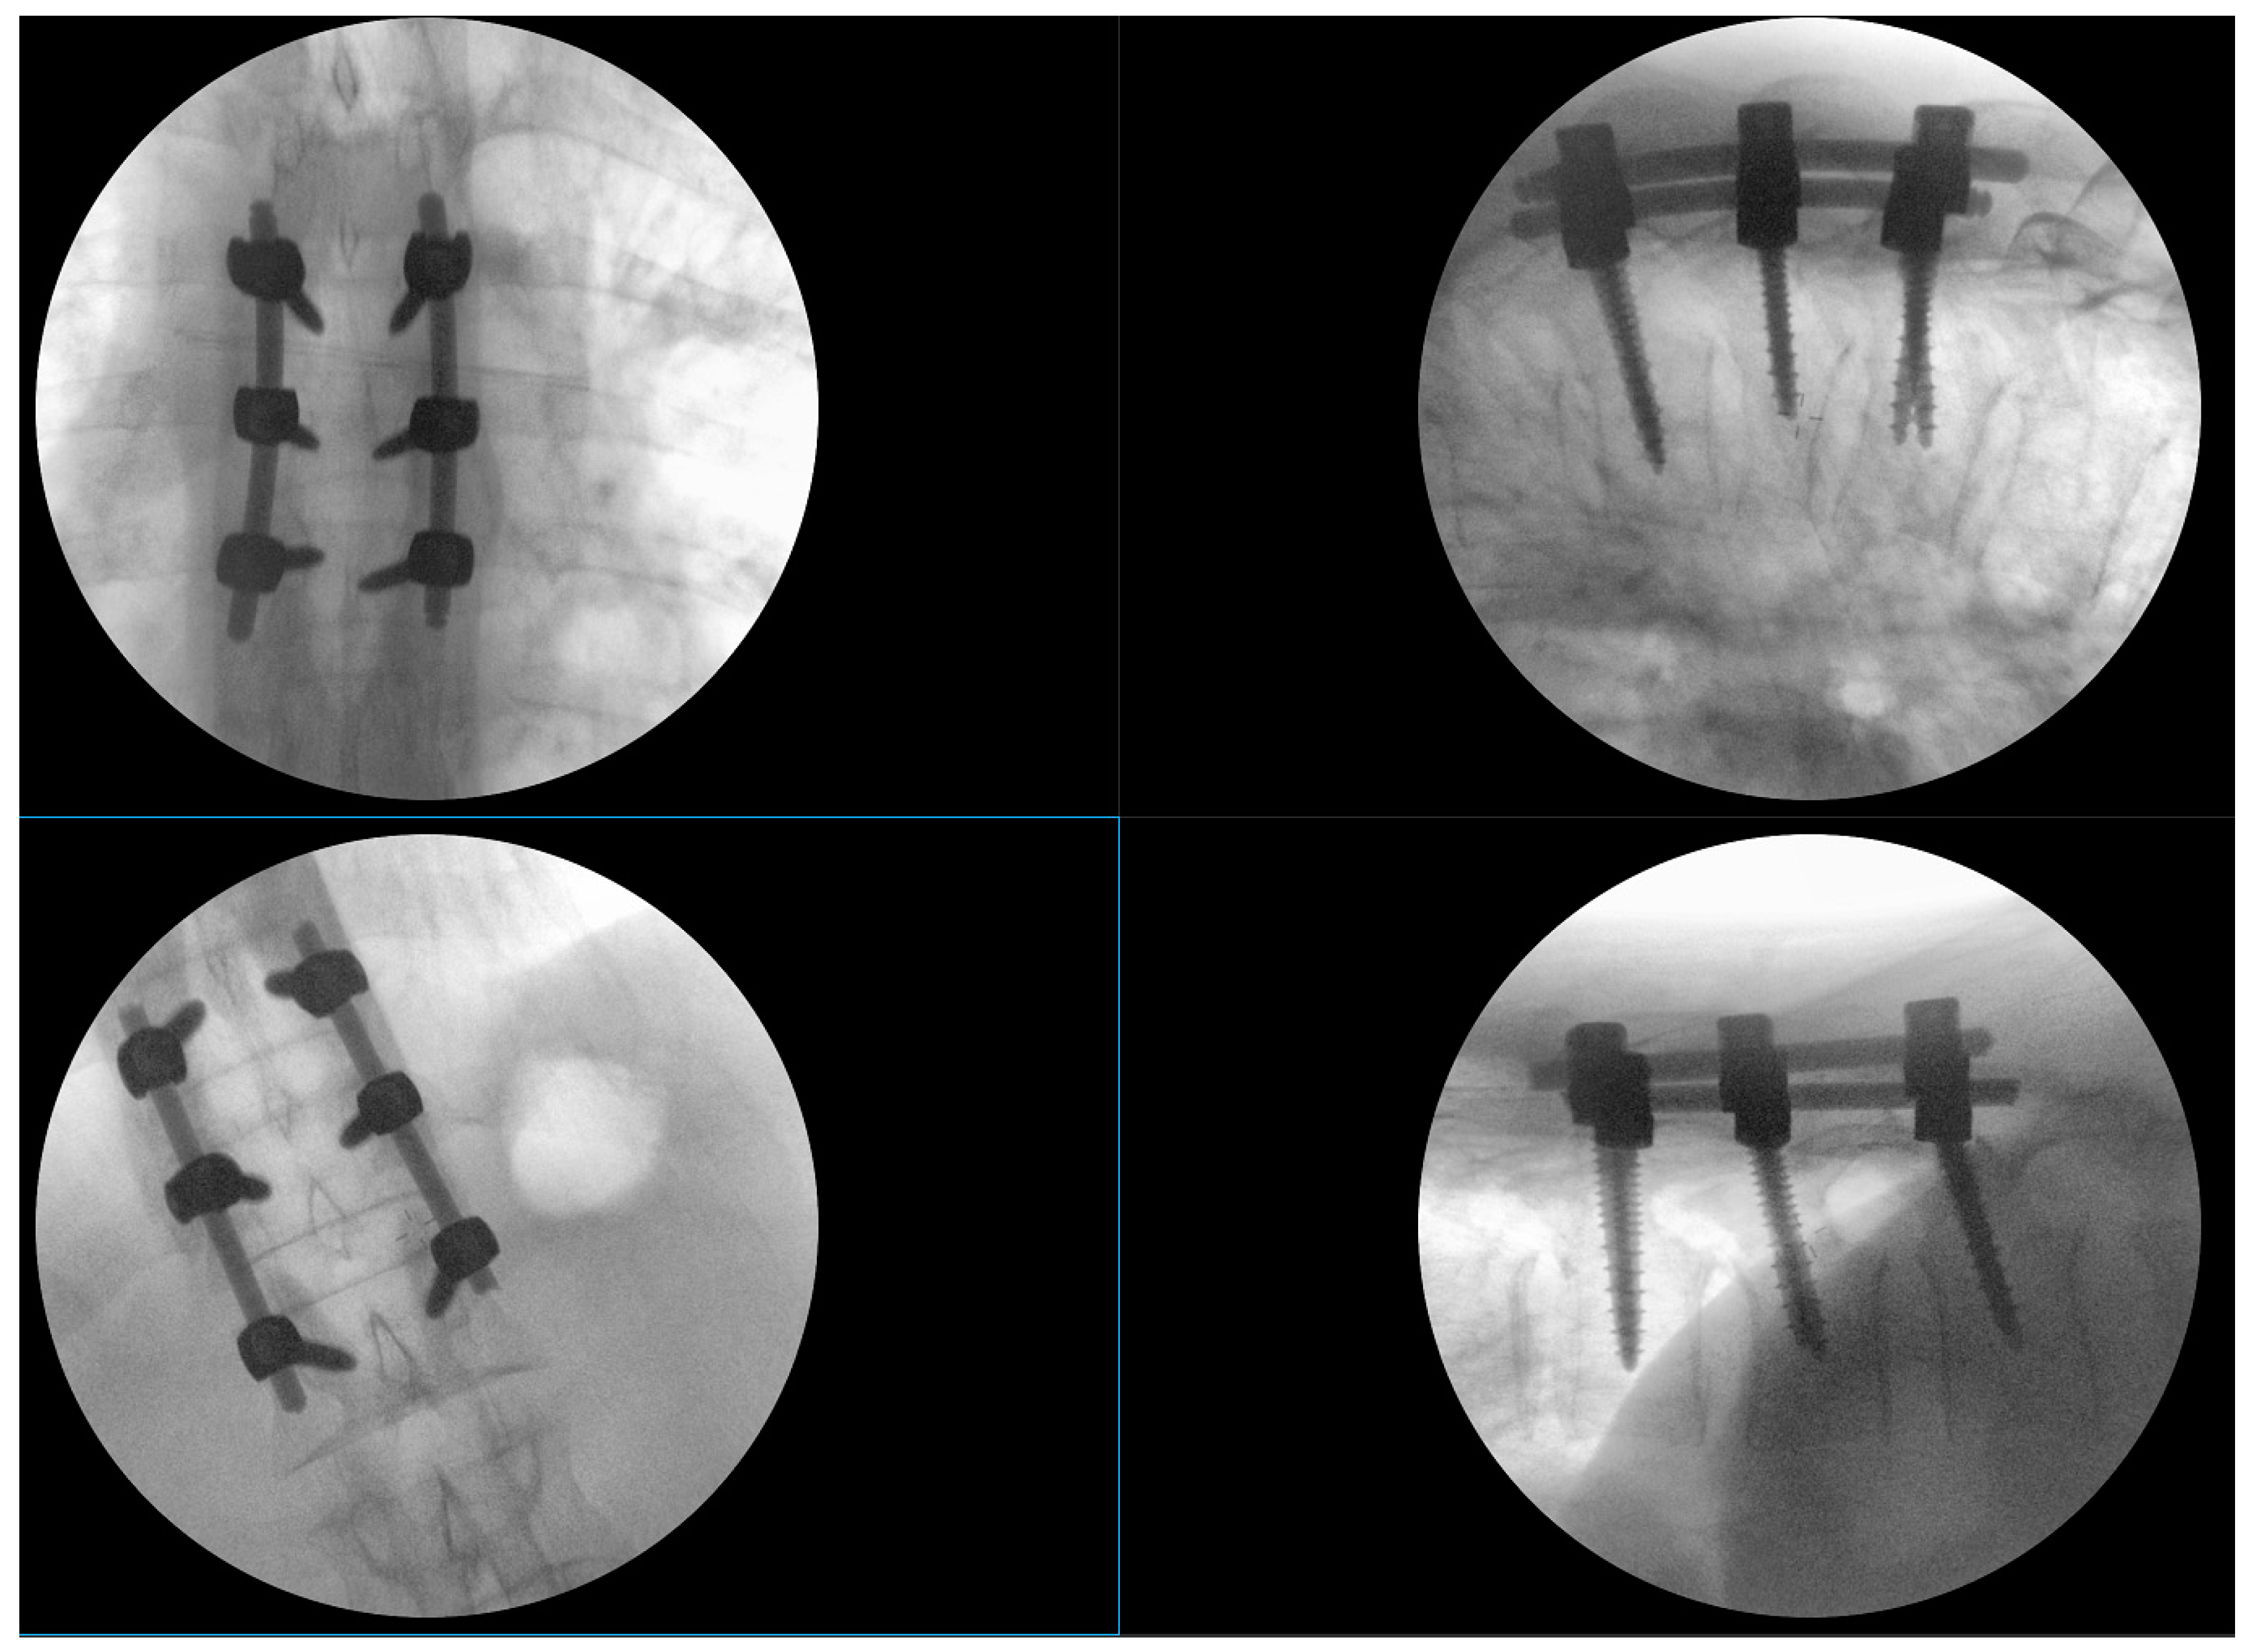

2. Case Report